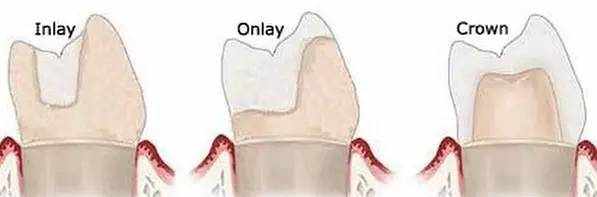

根管治疗结束后的牙齿需要酌情进行修复治疗。因为做根管治疗的牙齿大多有严重的龋坏或有很大的充填材料等薄弱点,治疗过程中及治疗后容易发生劈裂而导致失牙。因此可能需要用全冠、桩核冠或者高嵌体等不同形式的修复体来对牙齿进行保护,防止其折裂,同时恢复牙齿的功能。

答:根管治疗结束,治疗并没有结束。

因此根管治疗后的牙齿需要进行永久修复才可能用得长久。

• 根管治疗后的牙齿怎样修复?

随着口腔材料的进步,根管治疗后的修复方式日趋多样化,给了医生和患者更多的选择。总的趋势是更加美观,更加微创。

根管治疗后的牙齿修复方式包括直接充填,嵌体和全冠或加桩全冠修复。

根据材料可分为复合树脂,银汞合金,金合金,金属烤瓷,全瓷等等。

修复方案需要根据患者的年龄,牙齿缺损的大小,牙齿的位置,牙周状况,龋齿敏感性,美观需求等方面进行评估。

所以,一定是医生根据每个患牙条件以及患者需求来制定的。

根管治疗结束后的牙齿需要酌情进行修复治疗。因为做根管治疗的牙齿大多有严重的龋坏或有很大的充填材料等薄弱点,治疗过程中及治疗后容易发生劈裂而导致失牙。因此可能需要用全冠、桩核冠或者高嵌体等不同形式的修复体来对牙齿进行保护,防止其折裂,同时恢复牙齿的功能。

答:根管治疗结束,治疗并没有结束。

因此根管治疗后的牙齿需要进行永久修复才可能用得长久。

• 根管治疗后的牙齿怎样修复?

随着口腔材料的进步,根管治疗后的修复方式日趋多样化,给了医生和患者更多的选择。总的趋势是更加美观,更加微创。

根管治疗后的牙齿修复方式包括直接充填,嵌体和全冠或加桩全冠修复。

根据材料可分为复合树脂,银汞合金,金合金,金属烤瓷,全瓷等等。

修复方案需要根据患者的年龄,牙齿缺损的大小,牙齿的位置,牙周状况,龋齿敏感性,美观需求等方面进行评估。

所以,一定是医生根据每个患牙条件以及患者需求来制定的。